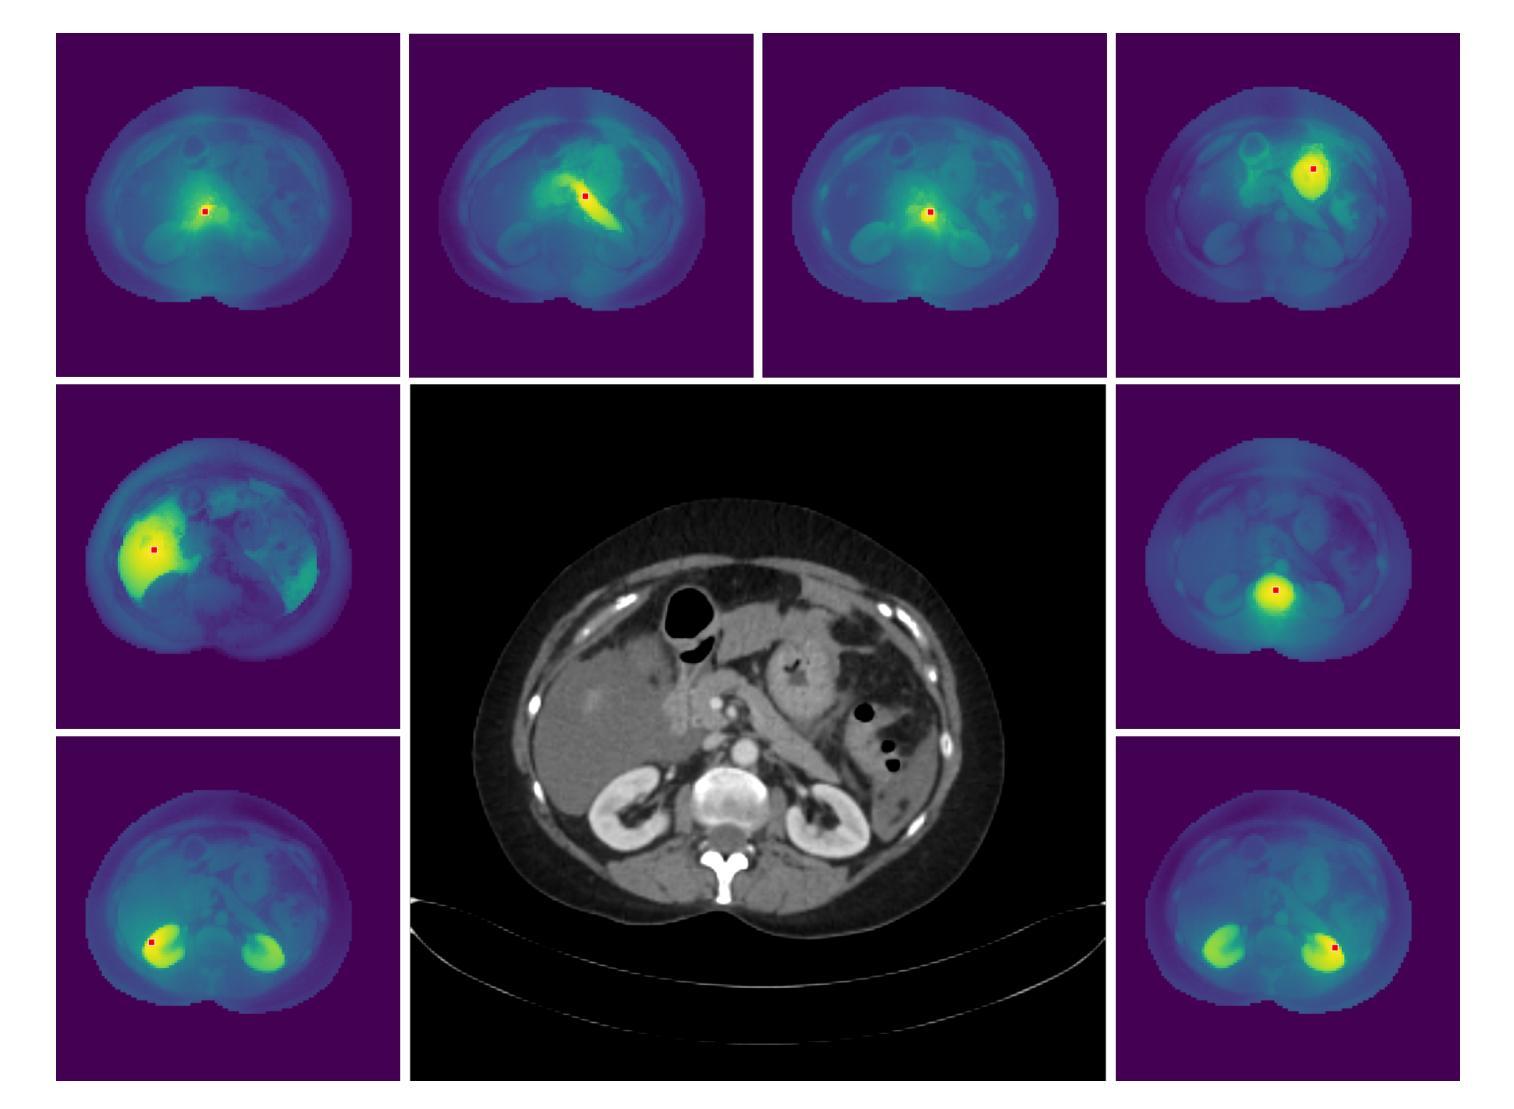

Cryo-RL: automating prostate cancer cryoablation planning with reinforcement learning

Authors:Trixia Simangan, Ahmed Nadeem Abbasi, Yipeng Hu, Shaheer U. Saeed

Cryoablation is a minimally invasive localised treatment for prostate cancer that destroys malignant tissue during de-freezing, while sparing surrounding healthy structures. Its success depends on accurate preoperative planning of cryoprobe placements to fully cover the tumour and avoid critical anatomy. This planning is currently manual, expertise-dependent, and time-consuming, leading to variability in treatment quality and limited scalability. In this work, we introduce Cryo-RL, a reinforcement learning framework that models cryoablation planning as a Markov decision process and learns an optimal policy for cryoprobe placement. Within a simulated environment that models clinical constraints and stochastic intraoperative variability, an agent sequentially selects cryoprobe positions and ice sphere diameters. Guided by a reward function based on tumour coverage, this agent learns a cryoablation strategy that leads to optimal cryoprobe placements without the need for any manually-designed plans. Evaluated on 583 retrospective prostate cancer cases, Cryo-RL achieved over 8 percentage-point Dice improvements compared with the best automated baselines, based on geometric optimisation, and matched human expert performance while requiring substantially less planning time. These results highlight the potential of reinforcement learning to deliver clinically viable, reproducible, and efficient cryoablation plans.

冷冻消融是一种对前列腺癌的微创局部治疗方法,它能在解冻过程中破坏恶性组织,同时保留周围的健康结构。其成功取决于冷冻探针放置的术前计划准确,以完全覆盖肿瘤并避免关键解剖结构。当前的规划是手动进行的,依赖于专家,并且耗时,导致治疗质量存在差异性且扩展性有限。在这项工作中,我们引入了冷冻强化学习(Cryo-RL),这是一种强化学习框架,它将冷冻消融计划建模为马尔可夫决策过程,并学习冷冻探针放置的最优策略。在一个模拟的临床约束和术中随机变化的环境中,代理程序会依次选择冷冻探针的位置和冰球直径。在肿瘤覆盖的奖励函数指导下,该代理程序学习了一种冷冻消融策略,该策略能够导致最优的冷冻探针放置,无需任何手动设计的计划。在回顾性前列腺癌病例中进行了评估,冷冻强化学习相较于基于几何优化的最佳自动化基线,Dice指数提高了超过8个百分点,并且与人类专家表现相匹配,同时规划时间大大减少。这些结果突出了强化学习在提供临床可行、可重复和高效的冷冻消融计划方面的潜力。

本文介绍了Cryo-RL这一强化学习框架在前列腺癌冷冻消融治疗计划中的应用。该框架能够模拟手术环境,自主规划冷冻探针位置和冰球直径,从而提高肿瘤覆盖率并缩短规划时间。在回顾性研究中,与几何优化等自动化方法相比,Cryo-RL在583例前列腺癌患者的应用中取得了超过8个百分点的Dice改善值,并达到了与人类专家相当的性能。